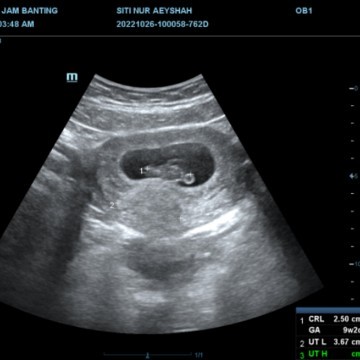

Semalam check up . Doc jumpa ketulan fibroid berukuran 3.67cm . Kalau 5cm baru operation. Nanti kk kena monitor ketulan tu takut kacau baby ke apa . Ada tak mommy² yang berpengalaman. Boleh share takk , #firstbaby